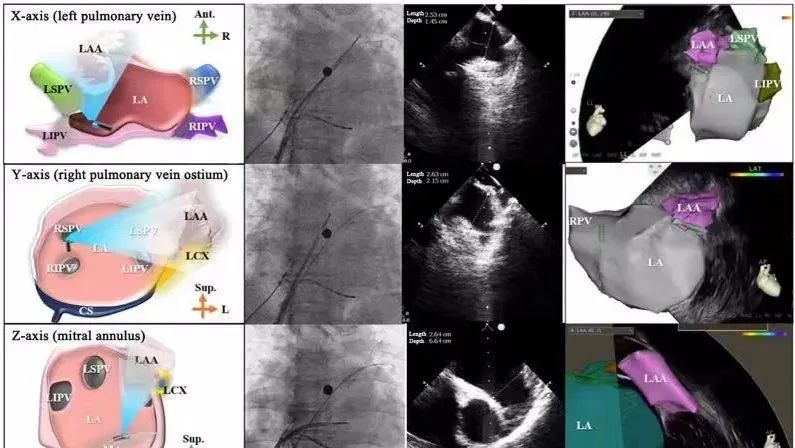

一種與心導(dǎo)管檢查相結(jié)合的超聲心動(dòng)圖診斷新興技術(shù),通過將超聲探頭置于心腔內(nèi)部,發(fā)射并接收超聲信號(hào),來精確獲取心臟解剖結(jié)構(gòu)、心臟血流動(dòng)力學(xué)等信息的實(shí)時(shí)成像。與其他影像技術(shù)相比,ICE技術(shù)具有操作簡單、無輻射、安全性高、手術(shù)效率高、實(shí)用等優(yōu)勢(shì),ICE在很大程度上有望取代經(jīng)食道超聲心動(dòng)圖(TEE),成為電生理和結(jié)構(gòu)性心臟病領(lǐng)域的理想成像方式。

目前ICE技術(shù)已被應(yīng)用于左心耳封堵、房顫射頻消融、二尖瓣成形、房間隔缺損封堵等多種心臟介入手術(shù),應(yīng)用場(chǎng)景主要圍繞心臟電生理、結(jié)構(gòu)性心臟病等領(lǐng)域,目前以電生理應(yīng)用為主。數(shù)據(jù)顯示,我國結(jié)構(gòu)性心臟病介入器械市場(chǎng)規(guī)模已從2017年的4億元增長至2021年的20億元,年復(fù)合增長率達(dá)48.3%;預(yù)計(jì)到2025年,該市場(chǎng)規(guī)模將達(dá)到104億元,可以預(yù)見ICE市場(chǎng)規(guī)模也將同步高速增長,未來市場(chǎng)發(fā)展空間廣闊。

心腔內(nèi)超聲(ICE)技術(shù)壁壘極高,國內(nèi)主要廠商核心部件仍舊為進(jìn)口,集成了超聲和圖像處理最前端技術(shù),包括超聲探頭、線纜、軟件成像算法等,是當(dāng)前內(nèi)窺超聲方向最具挑戰(zhàn)的領(lǐng)域。ICE的應(yīng)用經(jīng)歷了2D平面成像、3D三維立體成像、以及4D的實(shí)時(shí)三維立體成像階段。